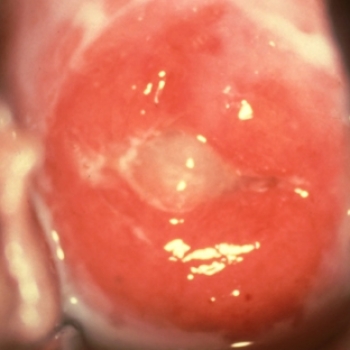

Enfermedades Venéreas 6190 0 Enfermedades Venéreas LINFOGRANULOMA VENEREO Clamidia tracomatis Por Dr. Mauro LEl linfogranuloma es una enfermedad poco frecuente en Costa Rica, es una infección que afecta principalmente los órganos genitales y los ganglios de la ingle, causada por una bacteria que se transmite a través de las relaciones sexuales.INTRODUCCION El linfogranuloma venéreo es una infección que afecta principalmente los órganos genitales y los ganglios de la ingle, causada por una bacteria que se transmite a través de las relaciones sexuales. ¿Cómo se llama el germen que provoca estas infecciones? El responsable es un tipo especial de Chlamydia trachomatis. FRECUENCIA El linfogranuloma es una enfermedad poco frecuente en Costa Rica. Es común en países con una pobre salud pública. CONTAGIO ¿Quiénes pueden contagiarse con esta infección? Cualquier persona puede adquirir la enfermedad si mantiene relaciones sexuales con un individuo infectado. Si la madre está infectada, el riesgo también está presente para el niño al momento del parto. ¿Cómo se contagia el linfogranuloma venéreo? Existen dos formas de adquirir este tipo especial de clamidia: 1. Vía sexual: se requiere una relación oral, vaginal o anal con penetración o sin ella, para que el germen pase de una persona infectada a una persona sana. 2. Vía materna: esta clamidia también se puede transmitir al niño en el momento del parto vaginal si la madre está infectada. Si en el acto sexual no se produjo la eyaculación, ¿hay riesgo de que la enfermedad se transmita? El riesgo de contagio siempre está presente, incluso en ausencia de eyaculación. Me diagnosticaron el linfogranuloma venéreo. ¿Puedo infectar a mis hijas en la convivencia del hogar? Existe un miedo generalizado de contraer o transmitir las enfermedades venéreas. A continuación presentamos una serie de actividades que no representan riesgo de contagio pero que, por equívoco, generan un enorme temor en la población. El linfogranuloma venéreo no se transmite en piscinas, gimnasios, servicios sanitarios o duchas, ni por alimentos o bebidas. Tampoco se transmite en actividades deportivas. No hay riesgo de contagio por visitar hospitales, asistir a reuniones o actividades con multitudes, compartir oficinas, aulas o medios de transporte como taxis, aviones y trenes, ni por tocar objetos como dinero o puertas. Tampoco se transmite por estornudos, tos o saliva. Esta enfermedad no se transmite por la utilización de prendas ni ropa interior; tampoco por el contacto con los animales, ni por tocar objetos contaminados con secreciones, ya sean asientos, vasos, cucharas, platos o máquinas, como las computadoras. Su transmisión requiere de un acercamiento sexual. De manera que no se transmite por caricias, apretón de manos, abrazos, ni en actividades artísticas como la danza o el baile. ¿Se puede contraer la infección al donar o recibir sangre? Al donar sangre no se corre ningún riesgo de contraer esta infección. Tampoco hay riesgo de infección si se recibe una transfusión sanguínea. MANIFESTACIONES ¿Es cierto que en algunos casos no se presentan síntomas? Según indican algunos estudios, más del 90% de los pacientes no presenta síntomas en las etapas iniciales de la enfermedad. Por ello, el paciente no recibe tratamiento y, sin saberlo, contagia a las personas con quienes mantiene vida sexual. Por lo general, el paciente consulta cuando la lesión se manifiesta en los ganglios de la ingle. ¿Cuándo aparecen los síntomas? Los primeros síntomas pueden aparecer de tres a veintiún días después de la relación sexual infectante. ¿Cuáles son los síntomas en el hombre? La primera manifestación consiste en un brote único, indoloro, que se ulcera con rapidez, ubicado en cualquier parte de los genitales masculinos; desaparece en unos días y usualmente pasa inadvertido. Dos a tres semanas después, los ganglios de la ingle se inflaman y, si no se instaura el tratamiento, se forman acúmulos de pus muy dolorosos, los cuales se rompen de manera espontánea. Estas manifestaciones suelen acompañarse de fiebre, escalofríos, náuseas, vómito, dolor articular y mal estado general. ¿Cuáles son los síntomas en la mujer? La primera manifestación consiste en un brote único, indoloro, que se ulcera con rapidez, ubicado en cualquier parte de los genitales femeninos; desaparece en unos días y usualmente pasa inadvertido. Dos a tres semanas después, los ganglios de la ingle se inflaman y, si no se instaura el tratamiento, se forman acúmulos de pus muy dolorosos, los cuales se rompen de manera espontánea. Estas manifestaciones suelen acompañarse de fiebre, escalofríos, náuseas, vómito, dolor articular y mal estado general. ¿Cuáles son los síntomas si la infección se produce en la zona anal? La primera manifestación consiste en un brote único, indoloro, que se ulcera con rapidez, ubicado en cualquier parte de la región anal; desaparece en unos días y usualmente pasa inadvertido. Dos a tres semanas después, los ganglios de la región anal se inflaman y, si no se instaura el tratamiento, se forman acúmulos de pus muy dolorosos, los cuales se rompen de manera espontánea. Estas manifestaciones suelen acompañarse de fiebre, escalofríos, náuseas, vómito, dolor articular y mal estado general. ¿Cuáles son los síntomas si la infección se produce por contagio a través del sexo oral? Esta ubicación es poco frecuente y la primera manifestación consiste en un brote único, indoloro, que se ulcera con rapidez, ubicado en cualquier parte de la región oral; desaparece en unos días y usualmente pasa inadvertido. Dos a tres semanas después, los ganglios del cuello se inflaman y, si no se instaura el tratamiento, se forman acúmulos de pus muy dolorosos, los cuales se rompen de manera espontánea. Estas manifestaciones suelen acompañarse de fiebre, escalofríos, náuseas, vómito, dolor articular y mal estado general. LINFOGRANULOMA VENEREO Y EMBARAZO ¿Cómo afectan estas infecciones el curso del embarazo? A la fecha, se considera que no provocan ninguna alteración durante los nueve meses del embarazo . ¿Cuáles madres pueden infectar al niño al momento de nacer? Aquellas que sufren de la enfermedad y no han recibido tratamiento al desencadenarse el parto vaginal. Si el niño nace por cesárea, no tiene riesgo de infección. ¿Cómo se diagnostica en una mujer embarazada? El diagnóstico de linfogranuloma venéreo suele ser difícil en cualquier mujer. Esta dificultad se acrecienta con los cambios hormonales y físicos que ocurren durante el embarazo, los cuales enmascaran aun más la infección. Por eso, cuando existen sospechas de la presencia de la infección, es mejor realizar las pruebas diagnósticas. ¿La mujer embarazada recibe el tratamiento durante el embarazo o posteriormente? La enfermedad se trata de inmediato, por cuanto en la actualidad existen medicamentos que no afectan el curso del embarazo ni el desarrollo del bebé. Así, se evitan complicaciones para la madre y para el niño. ¿Cuáles daños se producen si un niño se infecta al momento del parto? Lo más común es que desarrolle una conjuntivitis en las primeras dos semanas de nacido, la cual no representa riesgos importantes para el niño en el tanto reciba tratamiento adecuado y oportuno. En algunas situaciones, se pueden presentar cuadros de neumonía. Por lo general son muy molestos y con frecuencia requieren internamiento, pero rara vez son mortales. DIAGNOSTICO ¿Cómo se diagnostica esta enfermedad? El diagnóstico sigue siendo complejo. Lo ideal es tomar una muestra del sitio infectado, ya sea de la vagina, el cuello de la matriz, el caño de la orina, el recto, y analizarla. Sin embargo, no siempre se detecta el germen, aunque esté presente. ¿Es posible que las pruebas no determinen la presencia de la clamidia aun cuando la persona esté infectada? Es posible y relativamente frecuente. En caso de que los síntomas y los hallazgos físicos sean muy sugestivos, es recomendable brindar tratamiento, aun cuando las pruebas no comprueben la infección. ¿Se puede diagnosticar con la citología vaginal o Papanicolaou? El Papanicolaou se diseñó para diagnosticar lesiones precancerosas y cancerosas en el cuello del útero, no para detectar infecciones. Por eso, es poco frecuente que el Papanicolaou detecte esta infección. ¿Existe alguna prueba en sangre? No, lo cual es una lástima, porque el diagnóstico sería más fácil. TRATAMIENTO ¿Cuál es el tratamiento? Tanto en hombres como en mujeres el tratamiento se realiza con base en antibióticos. Inicialmente se creyó que la clamidia era muy vulnerable a antibióticos como la azitromicina y la doxiciclina. Sin embargo, cada vez se reportan más casos de resistencia y de cuadros que persisten por tiempos prolongados a pesar de tomar dosis repetitivas de estos antibióticos. En la actualidad, se adoptan diferentes esquemas y dosis para erradicar la bacteria y evitar las complicaciones. COMPLICACIONES ¿Cuáles son las complicaciones si no recibe tratamiento? El linfogranuloma puede generar una serie de complicaciones muy molestas, como la presencia de acúmulos de pus muy dolorosos en los genitales, en los ganglios de la ingle y en la región anal. Debido a que esta enfermedad daña los vasos linfáticos, con el tiempo el paciente puede experimentar hinchazón de los tejidos genitales. También se ha descrito que, años después de los síntomas iniciales, se pueden producir estrechamientos del recto, así como fístulas o comunicaciones anormales entre el recto y la vagina. PREVENCION ¿Cómo se puede prevenir el contagio? Como hemos mencionado a lo largo de este documento, las enfermedades de transmisión sexual son muy difíciles de prevenir porque no siempre dan síntomas y porque la vida sexual es muy compleja y pleomórfica. Comúnmente las personas olvidan las normas mínimas de prevención, las cuales suelen ser bien conocidas. Entre estas medidas se destacan: 1. Evitar relaciones sexuales con personas de riesgo, como las prostitutas. 2. Utilizar el preservativo de manera estricta, correcta y constante. 3. Consultar ante la presencia de cualquier molestia genital. 4. Evitar las relaciones sexuales cuando se sufre de molestias genitales. 5. Realizarse chequeos periódicos si se mantiene una relación sexual con una pareja no habitual. 6. Ante el diagnóstico de linfogranuloma venéreo, avisar a las personas con quienes se mantuvo vida sexual durante el periodo de riesgo que el médico señale. 7. Efectuarse chequeos cuando se cambia de pareja sexual, o bien, cuando se conoce que la pareja habitual ha tenido relaciones sexuales con una tercera persona. ¿El preservativo es eficaz para evitar el contagio? En términos generales, es altamente efectivo. No obstante, es común que el preservativo se use de manera errónea, y esto expone al riesgo de contagio. Además, la protección no es absoluta. Siempre existen casos en que, a pesar del uso correcto del preservativo, la enfermedad se transmite. Si una persona tuvo el linfogranuloma venéreo, ¿está protegida de una nueva infección? Claro que no. Una persona puede infectarse varias veces en la vida, por cuanto esta enfermedad no produce inmunidad natural. Así, los pacientes que han sido tratados pueden adquirir de nuevo el germen si tienen contacto sexual con personas infectadas. ¿Existe alguna vacuna para evitar el contagio? Desafortunadamente no existen vacunas para evitar el contagio. Por eso la prevención y el tratamiento oportuno son fundamentales. RELACION CON OTRAS ENFERMEDADES Me diagnosticaron linfogranuloma venéreo. ¿Tengo probabilidad de tener otras enfermedades venéreas? El linfogranuloma venéreo se ha asociado a otras enfermedades de transmisión sexual. Según menciona la literatura internacional, cuando hay una infección por clamidia aumenta la posibilidad de contraer sífilis, sida y hepatitis C. Sin embargo, se sabe que es posible su coexistencia con cualquier otra enfermedad venérea. Por eso, siempre es prudente realizar estudios completos de infecciones sexualmente transmisibles, entre ellas sida, virus del papiloma, herpes genital, hepatitis B, gonorrea y sífilis. ¿Hay alguna relación entre el virus del papiloma y el linfogranuloma venéreo? Recientes investigaciones sugieren intrincadas relaciones entre estos gérmenes, a saber: • El linfogranuloma venéreo provoca que el virus del papiloma sea más difícil de tratar. • El linfogranuloma venéreo aumenta la probabilidad de que el virus del papiloma desencadene un proceso canceroso. • El linfogranuloma venéreo aumenta la probabilidad de que el virus del papiloma desencadene cuadros de condilomas externos. • Si coexisten el linfogranuloma y el virus del papiloma, se debe diseñar un plan integral de tratamiento. ¿Hay alguna relación entre el sida y el linfogranuloma venéreo? Nuevos estudios indican que son probables ciertas interacciones entre estas enfermedades, a saber: • El paciente con linfogranuloma venéreo tiene mayor probabilidad de contagiarse con el virus del sida. • Además, una vez contagiado tiende a transmitir el sida más fácilmente. • El paciente con sida contrae con mayor facilidad el linfogranuloma venéreo. • En el paciente con sida, el linfogranuloma venéreo progresa de manera acelerada y provoca complicaciones más fácilmente.